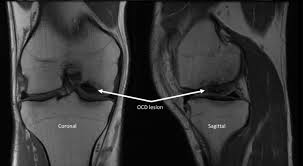

Use your time efficiently and maximize your retention of key facts and definitions with study sets created by other students studying medial femoral condyle. Given its location, these are also the easiest cartilage defects to repair. Normal irregular ossification of the femoral condyles was present in 66% of the boys and 44 % of the girls 1 in a review of knee radiographs of 147 healthy, asymptomatic children between the ages of 3 and 13 years. The flap is marked by identifying the vascular plexus on the medial condyle and incorporating a component of the network in the flap. Primary osteonecrosis of the femoral condyle shares several features with insufficiency fractures, including predominance in elderly women with factors responsible for mechanical stress (varum, obesity, trivial trauma), mechanical pain, and increased radionuclide uptake. The femoral condyle allograft has been used for resurfacing cartilage defects with mature hyaline cartilage for several decades, with very high success rates. Osteonecrosis of the medial femoral condyle presents as a sudden onset of pain on the medial side of the knee. An articular cartilage injury, or chondral injury, may occur as a result of a pivot or twist on a bent knee, similar to the motion that can cause a meniscus tear.

Medial condyle of femur from wikipedia, the free encyclopedia the medial condyle is one of the two projections on the lower extremity of femur, the other being the lateral condyle. The lateral condyle was involved in 44 % and the medial condyle in 12 %. Palpable as a hard, rounded bump to the inside of either knee joint, they are one of two condyles at the bottom of each leg bone, the other being the lateral femoral condyle. This adaptable graft option is most commonly used with oats or shell techniques to restore cartilage in the knee, but can also be used to for cartilage restoration of other joints. In a review of 79 patients with this disease, performed to establish guidelines f … The medial femoral condyle is supplied by a plexus of vessels from the descending genicular artery and the medial superior genicular artery. The medial condyle is larger than the lateral (outer) condyle due to more weight bearing caused by the centre of mass being medial to the knee. Root tear (radial tear) of the medial meniscus mild or moderate knee arthritis According to the hospital for special surgery, the medial femoral condyle is the inside of the knee, and health issues dealing with it can be treated. Osteonecrosis of the medial femoral condyle can be treated in a variety of ways depending on the stage of the disease. The medial condyle is named for its location on the inside of the knee, closer to the midline of the body, while the lateral condyle is found on the outside of the knee, away from the midline of the body. In the knee, chondromalacia is usually related to injury, overuse of the knee, and poorly aligned muscles and bones around the knee joint. Your knee mri will often show a:

Chondral injuries may accompany an injury to a ligament, such as the anterior cruciate ligament. Your knee mri will often show a: Schatzker i tibia plateau fracture. Osteonecrosis of the medial femoral condyle presents as a sudden onset of pain on the medial side of the knee. Normal irregular ossification of the femoral condyles was present in 66% of the boys and 44 % of the girls 1 in a review of knee radiographs of 147 healthy, asymptomatic children between the ages of 3 and 13 years. However, two of the patients had one or more fractures missed when they first presented. A bone fracture at this location is termed a femoral condyle fracture. According to the hospital for special surgery, the medial femoral condyle is the inside of the knee, and health issues dealing with it can be treated.

Of the six patients who had suffered an isolated fracture of their medial condyle, four of the patients had their fractures diagnosed on the first visit. The lateral condyle was involved in 44 % and the medial condyle in 12 %. It acts to support a significant amount of the patient's body weight. Cartilage can be focally damaged, producing a pot hole in the joint surface, when the knee ligaments are injured. Osteonecrosis of the medial femoral condyle presents as a sudden onset of pain on the medial side of the knee. A bone fracture at this location is termed a femoral condyle fracture. The femoral condyle is a thickened area of the femur just above the knee. One presumed mechanism of injury is a stieda fracture (avulsion injury of the medial collateral ligament at the medial femoral condyle). Root tear (radial tear) of the medial meniscus mild or moderate knee arthritis Coronal plane fracture of the lateral femoral condyle. The lesions were located on the medial femoral condyle in 8 (72.7%) cases and on the medial tibial plateau in 3 cases (27.3%). The medial femoral condyles are the bony protrusions on the inside edge of the bottom of the femur bone in each thigh. Based on the patient's antalgic gait and radiographic findings, the patient was instructed on the proper use of crutches and referred to an orthopaedic surgeon for appropriate management.